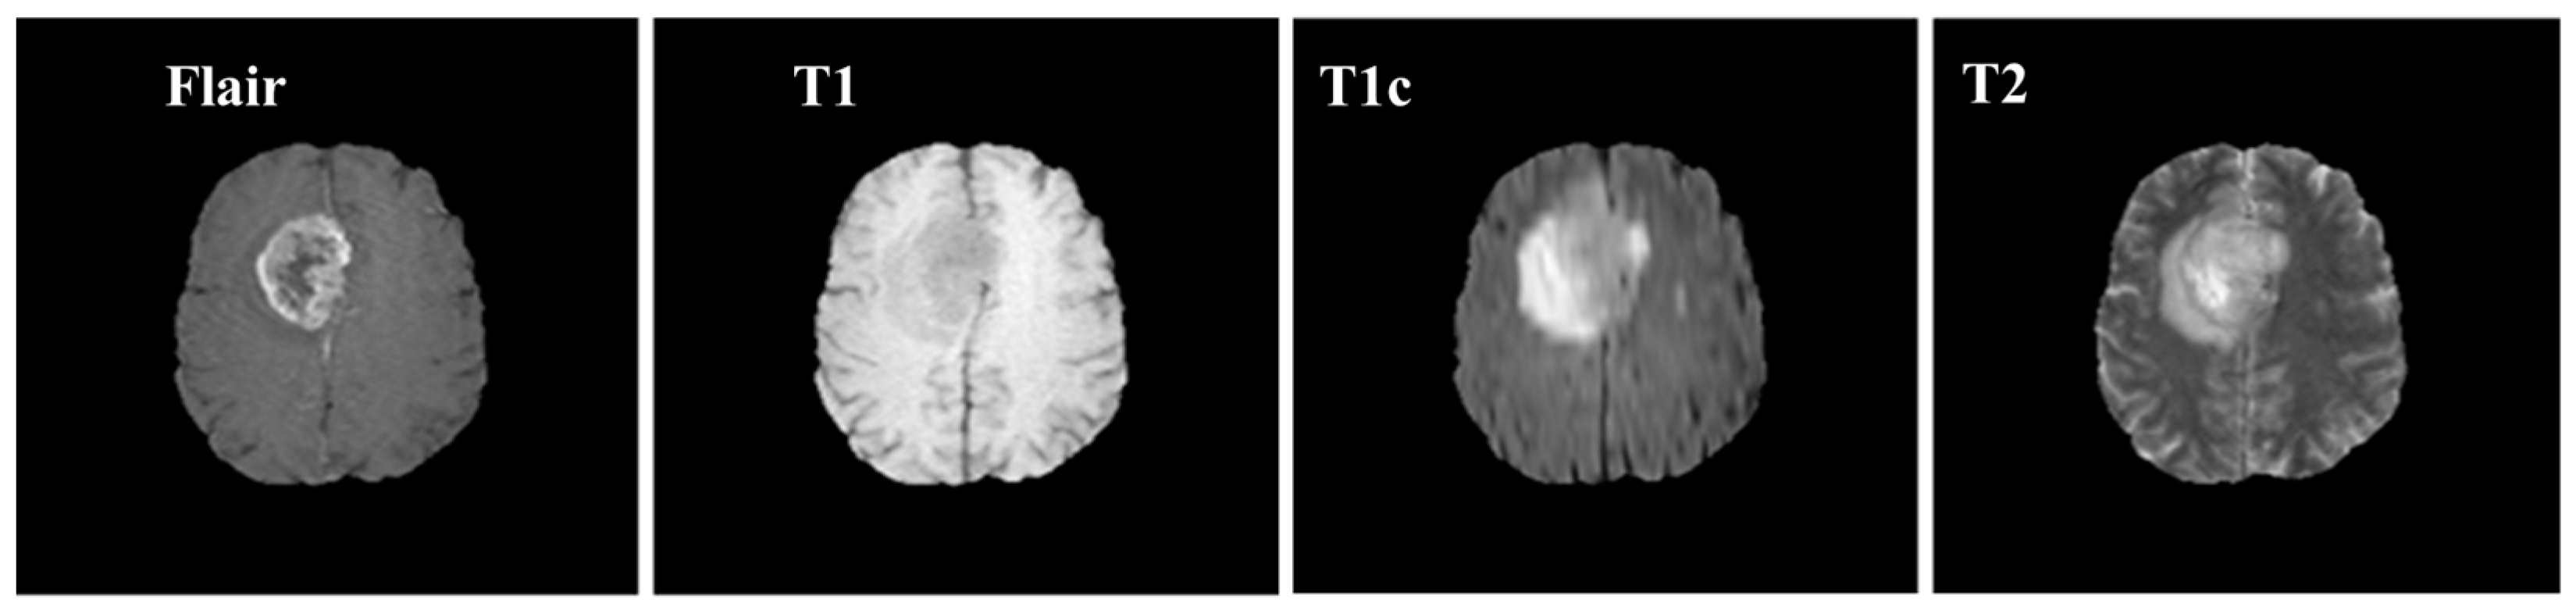

Samples of these four modalities (T1, T2, T1c, Flair) are presented in Figure 6. All four modalities have 620 MR images which make a total of 239,320 MR images for all 384 cases and a total of 169,880 MR images 274 train images as shown in Table 2. In BraTS dataset, labels are provided only for the train images so only train images are used for experiments. The dataset is divided into 60% for training, 20% for validation and 20% for the testing. BraTS provides data in MetaImage (.mha) format which is used to store 3D medical images. For each modality of every case, there are 155 slices with 240 × 240 pixel dimensions which are stored in a single mha file.

Figure 6. Sample MR images of T1, T2, T1c and Flair modalities.